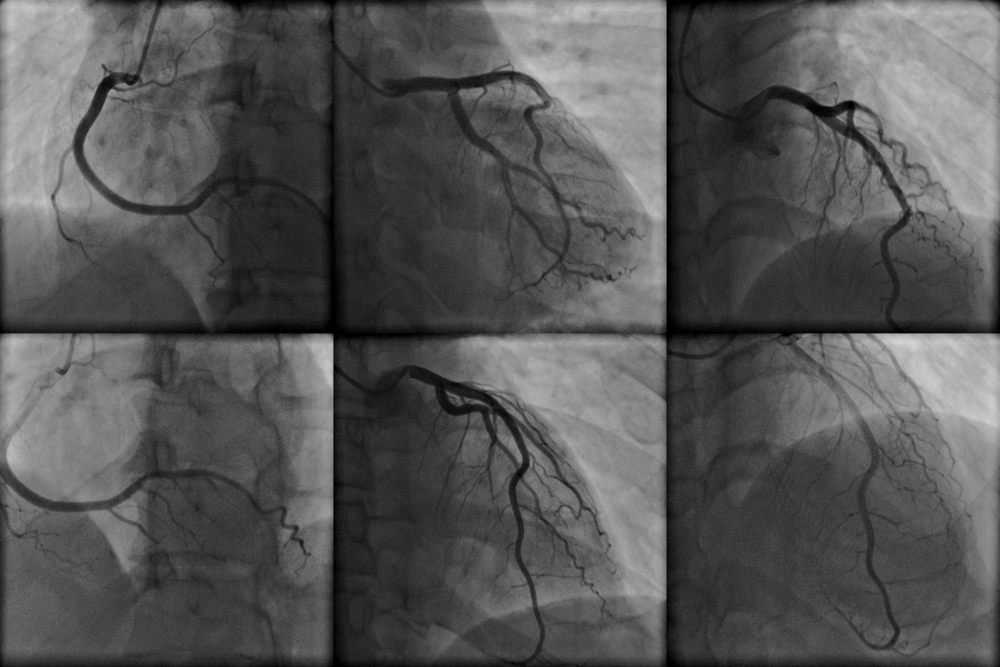

- Для ангиографии в катетер вводится рентгеноконтрастное вещество, которое позволяет визуализировать желудочки и коронарные сосуды. Специалист анализирует их состояние, делает снимки и формирует заключения. Во время съемки врач может попросить пациента задержать дыхание, сделать глубокий вдох или покашлять.

- ангиография – используется для получения изображений камер сердца, коронарных артерий, легочных артерий и аорты;

- Коронарография: Это визуализация коронарных артерий с помощью контрастного вещества. Оценка состояния коронарных артерий позволяет выявить стенозы (сужения), окклюзии (закупорки) и другие аномалии, которые могут привести к ишемической болезни сердца.